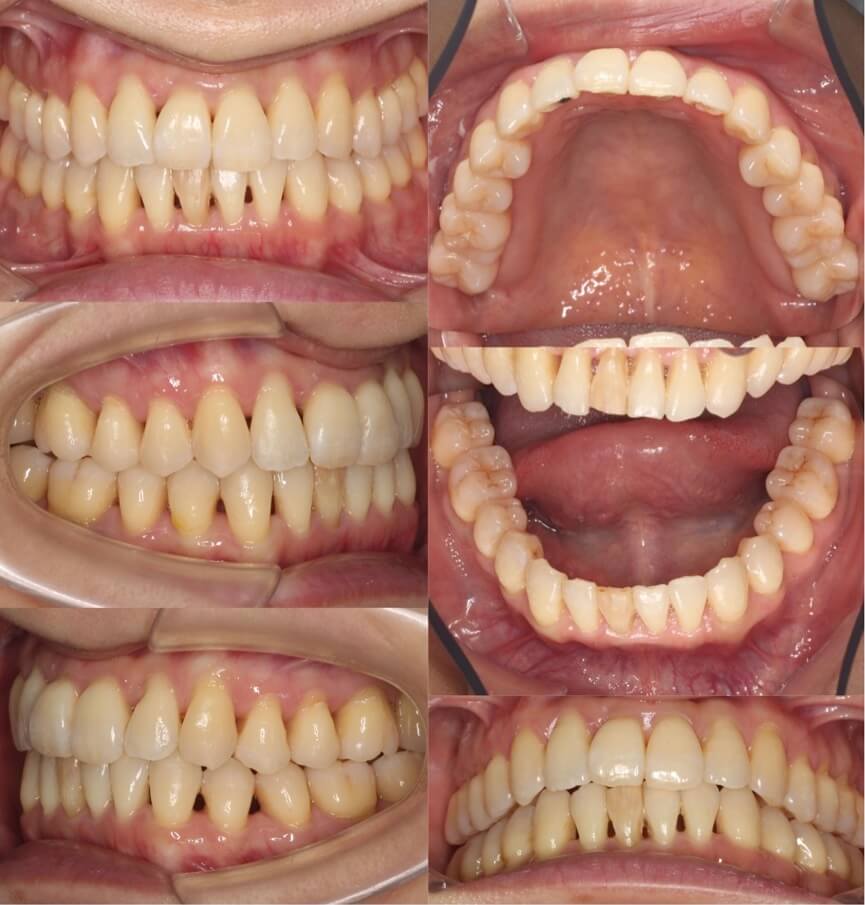

46歳女性・唇側矯正装置・抜歯

<症例概要>

主訴:前歯と口元の突出

年齢・性別:43歳女性

住まい:千葉県佐倉市

症状:叢生・上下顎前歯唇側傾斜

治療方針:上左右5番・下左右4番(計4本)

治療装置:唇側矯正装置

固定装置:ナンスホールディングアーチ

治療期間:3年

リテーナー:下フィックス+上下クリアタイプ

治療費用:968,000(税込)

代表的副作用:痛み・治療後の後戻り・歯根吸収・歯髄壊死・歯肉退縮

▶︎その他の副作用

前歯の突出のため口が閉じづらいことを気にされていて矯正治療を希望された患者さんです。年齢的に抜歯を行うか迷ったのですが、患者さんの主訴を優先して抜歯矯正により前歯を後方移動させました。抜歯部位については、上の歯並びは治療歯である第二小臼歯(5番)を選択しています。その分、治療期間は3年を超えてしまったのですが、理想的な横顔になりました。